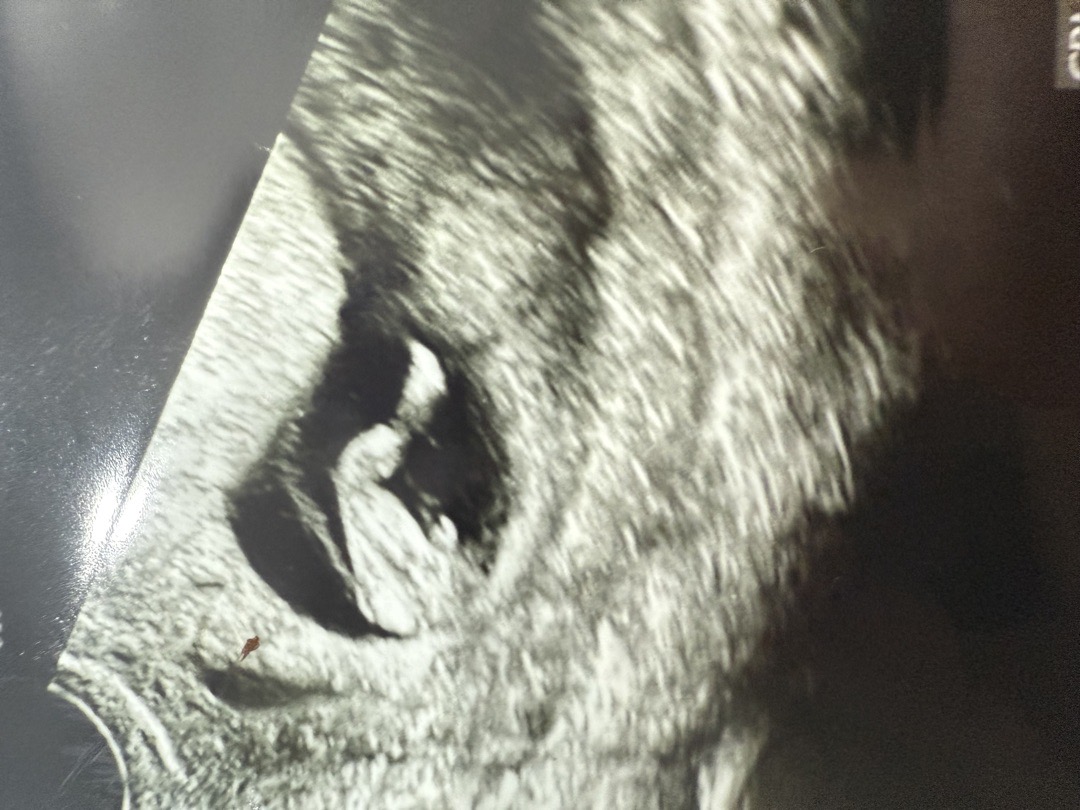

10주차 성별

10주차 6일이에요 초음파 보시더니 아들같다고 하시네요 제가 볼때도 튀어나와있긴하던데 10주차에도 정확하게 알 수가 있는건가용..?

저도 그렇게 생각하는데ㅠㅠ 다시 되물었는데도 거의 아들이라고 봐야된대요

벌써 알수있나요!? 저두 10주 5일차에 허벅지사이에 보여서 남자냐하니 아직 알수없다 하셨는데

그러니까요 저도 의아했어요 거의 확신하면서 말씀하시길래 ㅠ